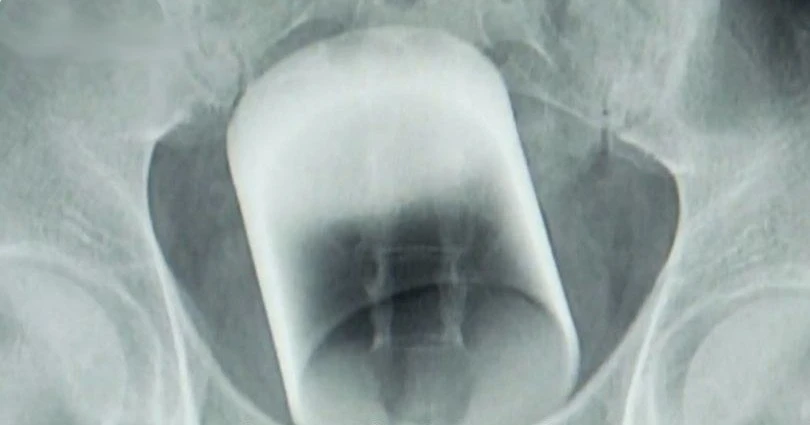

Житель Уфы вставил стакан в зад во время праздника 23 февраля. По его словам, он просто поскользнулся и случайно упал прямо на посуду задом.

Дмитрий отмечал День защитника Отечества с приятелем: выпили, заели и перешли к "конкурсам". В итоге стакан каким-то образом оказался в его прямой кишке.

Друзья безуспешно пытались извлечь стекляшку, так что экстремалу пришлось звать скорую.

Видимо, злополучный стакан подставил подножку и нагло атаковал цель.